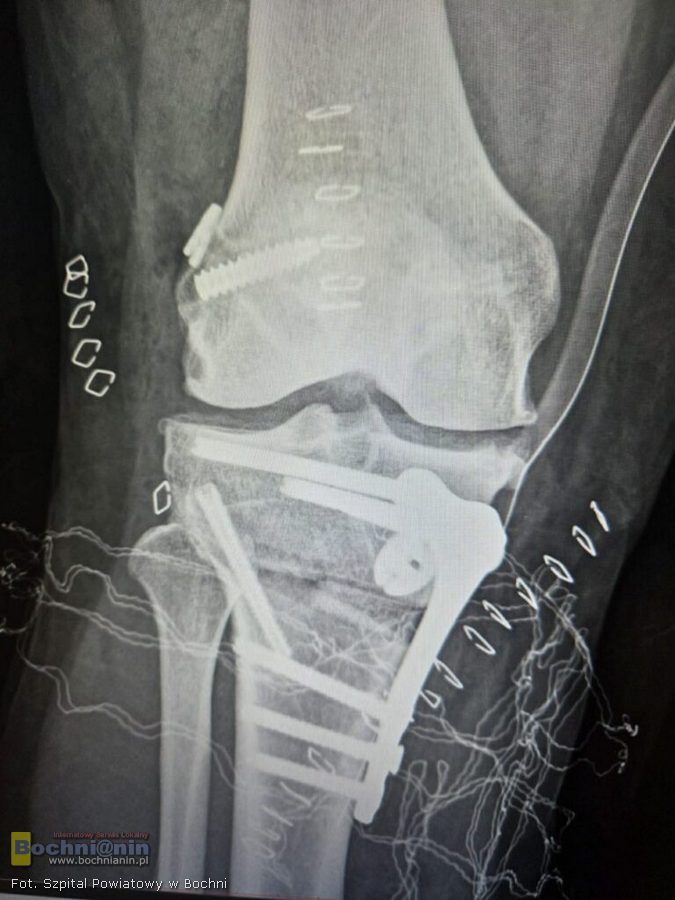

Aby wyeliminować problem konieczne było stworzenie modelu 3D i precyzyjne przemodelowanie kości piszczelowej. Z pomocą przyszedł Jakub Piękoś inżynier medyczny z Warszawy, który zaprojektował komputerowo i precyzyjnie wymierzył przycięcie kości w kilku płaszczyznach. Stworzony model 3D posłużył lekarzom jako przewodnik śródoperacyjny.

– Musieliśmy przyciąć kość w takich kierunkach, aby po wprowadzeniu płytki, zrekonstruowane więzadło zostało utrzymane choćby w przypadku wykonywania ruchów skrętnych. Operacja zakończyła się sukcesem – mówi lek. Mateusz Job, któremu przy wykonywaniu zabiegu towarzyszyli także lek. Michał Budziakowski i lek. Bernard Bukowski.